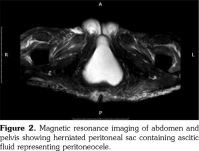

We performed extended investigations that showed normal blood albumin level. Tumor markers were significant only for an elevated serum cancer antigen 125 (CA-125) (80 U/L normal <35). Work-up for TB was negative including adenosine deaminase and polymerase chain reaction in ascitic sampling. Cytology was negative for malignant cells. We conducted computed tomography scan for the chest, abdomen and pelvis with contrast showing massive ascites with ill-defined omental thickening related to the anterior abdominal wall. A cystic lesion was seen at perineal region, minimal bilateral pleural effusion and massive abdominal ascites. Laparotomy and biopsy were performed revealing fat necrosis. Subsequently, magnetic resonance imaging of the abdomen and pelvis was conducted but it was insignificant apart from massive ascites with adhesions. No ovarian masses were observed (Figure 1). In lower perineal region, herniating peritoneal sac was noted containing ascitic fluid representing peritoneocele (Figure 2).